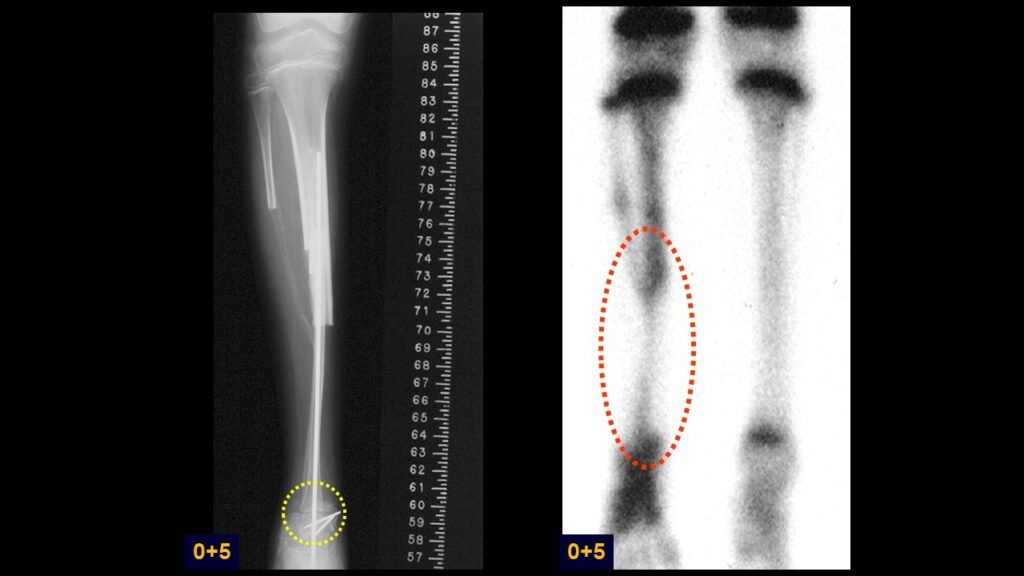

Giroplastia de Van Ness